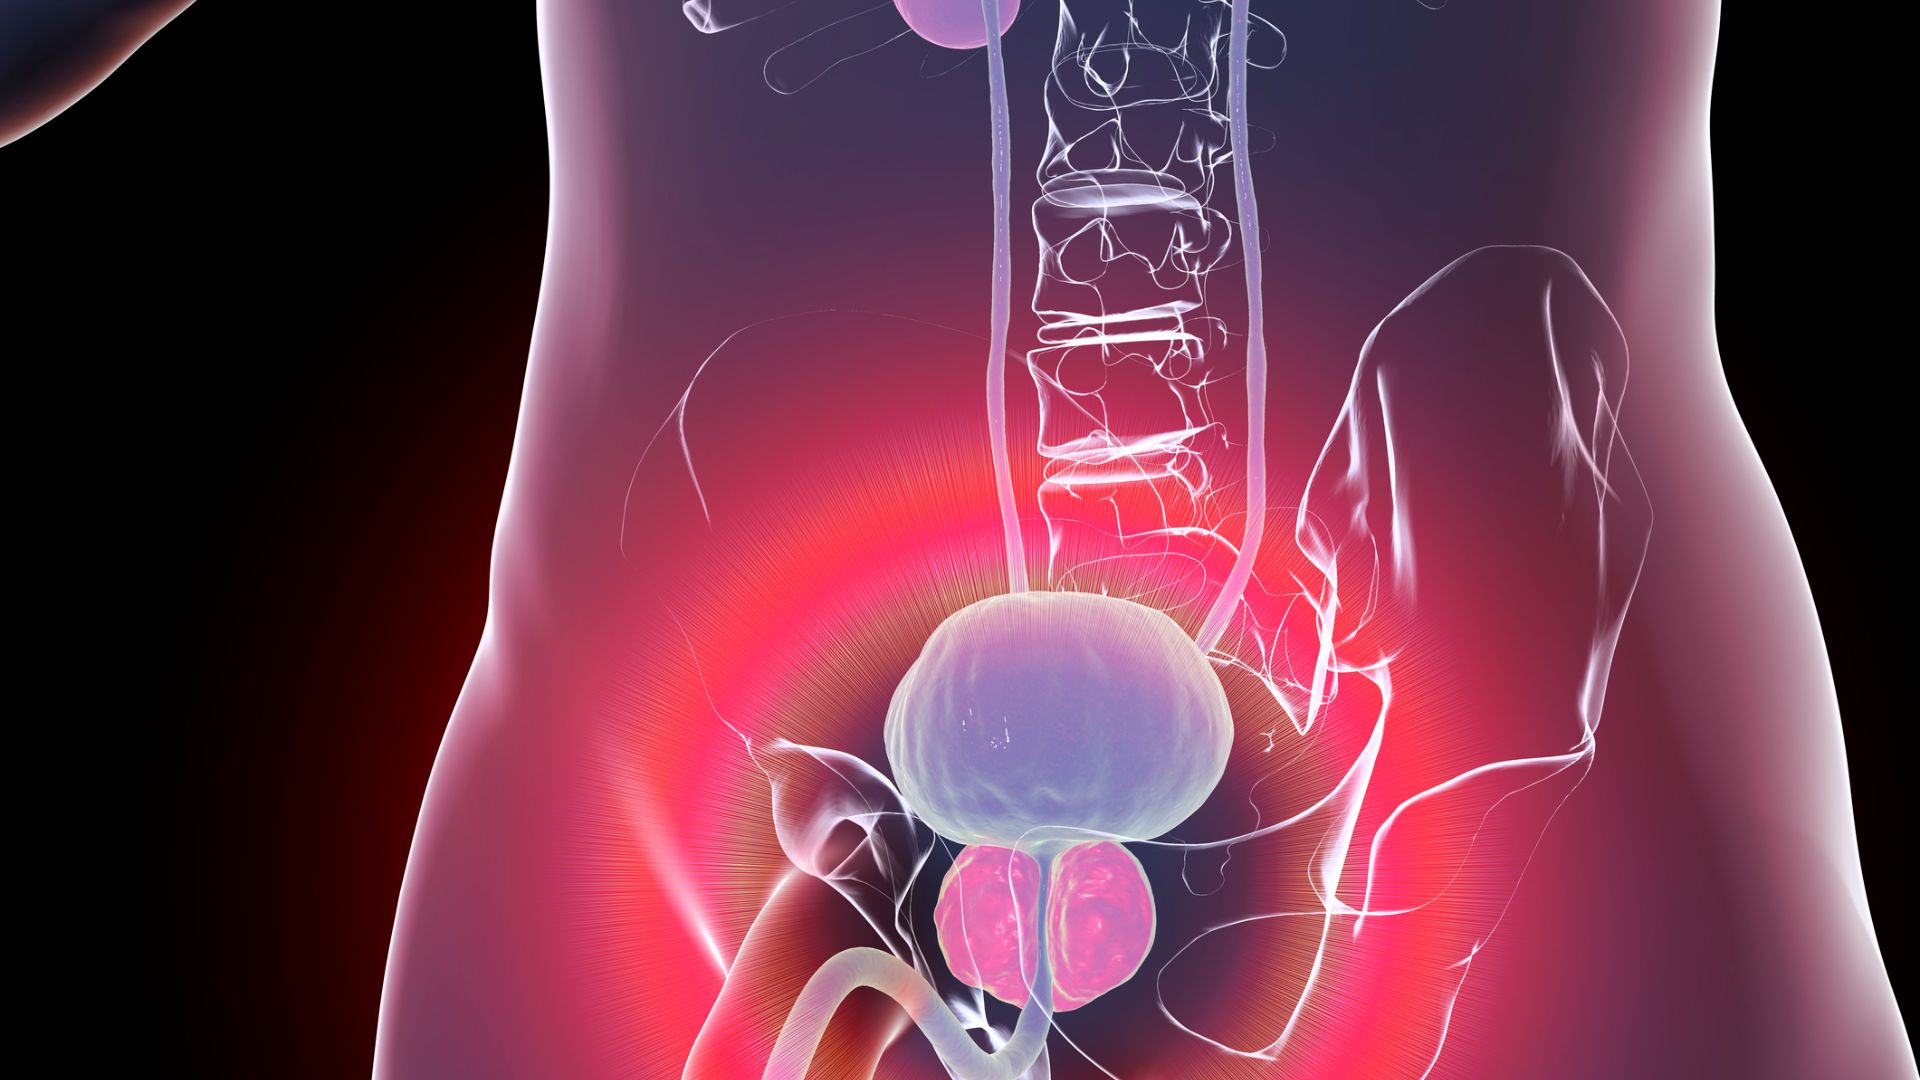

© Getty images

En vieillissant, la prostate grossit de manière naturelle, non cancéreuse, c’est ce qu’on appelle l’Hyperplasie Bénigne de la Prostate ou HBP. Cette maladie est aussi appelée adénome de la prostate. Lorsqu’elle comprime le canal urinaire (urètre), l’HBP provoque des troubles plus ou moins invalidants de la fonction urinaire.

Elle touche plus de 50% des hommes de plus de 60 ans. Les traitements médicamenteux disponibles permettent d’améliorer les symptômes des patients, au prix d’un risque élevé d’effets secondaires et donc d’abandon1.

L’embolisation des artères prostatiques (EAP) consiste à utiliser la voie naturelle des vaisseaux sanguins pour atteindre la prostate sans chirurgie. Après avoir repéré les artères prostatiques, le radiologue Interventionnel y injecte des petites particules de la taille d’un grain de sable, bouchant ainsi les artères nourricières de la prostate. La glande prostatique va rétrécir progressivement par manque de sang ce qui a pour effet de réduire les symptômes urinaires associés.

L’objectif de l’étude PARTEM était de comparer les effets jusqu’à 2 ans de ce traitement mini-invasif par rapport au traitement médicamenteux chez des patients porteurs d’un adénome supérieur à 50 g.

Les investigateurs ont inclus 90 patients dans 10 hôpitaux français entre septembre 2016 et février 2020. Tous les patients présentaient des symptômes urinaires gênants mesurés à l’aide du questionnaire IPSS (International Prostatic Symptom Score)2, malgré un traitement par alpha-bloquants seul.

Par tirage au sort (randomisation), la moitié des patients (44) a été traitée par une EAP et l’autre moitié (43) par l’association dutastéride 0,5 mg / tamsulosine 0,4 mg par jour (médicament combiné).

Après 9 mois, la réduction des symptômes a été plus importante dans le groupe EAP que dans le groupe médicament combiné, et la différence était significative tant cliniquement que statistiquement. Une différence en faveur de l’EAP a également été observée sur les symptômes sexuels. La procédure, réalisable lors d’une hospitalisation de jour, n’a eu que des effets secondaires mineurs dans les suites immédiates.

Cet essai randomisé positionne donc l’embolisation prostatique comme une alternative crédible à un traitement médicamenteux combiné, chez les patients porteurs d’un adénome de taille modérée à grosse, résistant à un traitement initial par alpha-bloquants.